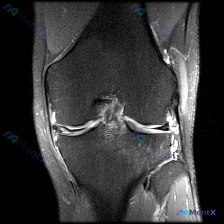

看到这张膝关节冠状位MRI,一开始只关注到半月板异常,系统评估后发现其实是非常典型的复合损伤,我整理了完整分析思路,和大家分享一下。 病例核心信息 这是一张脂肪抑制水成像序列(质子密度或T2加权)的膝关节冠状位MRI,我们按照系统顺序整理发现: 1. 骨骼:股骨远端、胫骨近端骨皮质连续无移位骨折,但...

看到一个很有代表性的膝关节MRI读片病例,整理资料和分析思路分享给大家。 病例基础信息(影像资料) 这是一张膝关节MRI冠状位影像,序列为对水肿和液体敏感的脂肪抑制质子密度加权像/T2压脂像,核心影像发现如下: 1. 骨骼:胫骨近端内侧平台关节面下方可见边界模糊的片状高信号,无骨皮质断裂或塌陷,符合...